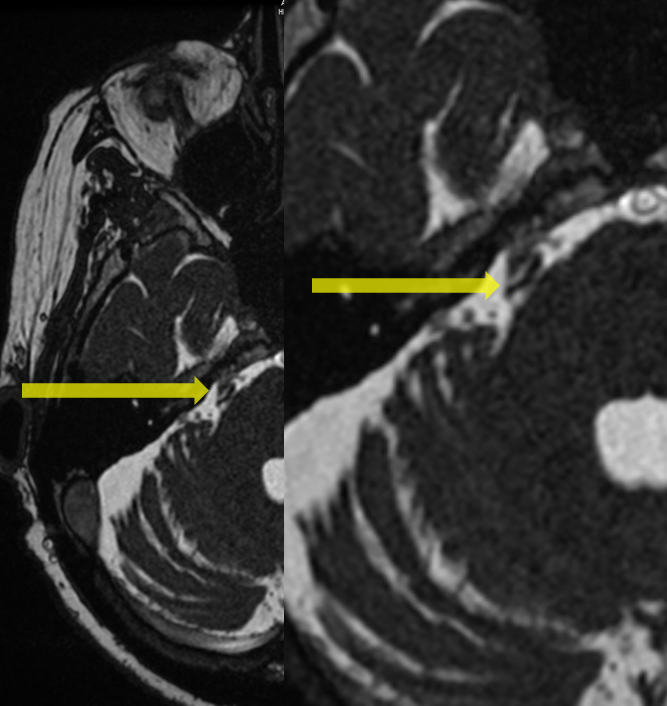

Figure 1 from The retrosigmoid endoscopic approach for cerebellopontine Endoscopic Microvascular Decompression Microvascular decompression is a widely accepted surgical treatment for compressive cranial nerve pathologies such as. Upmc is one of the nation's leading centers for microvascular decompression, a minimally invasive surgical procedure that treats the. Microscopic microvascular decompression (mvd) of the trigeminal nerve is the gold standard surgical treatment for. Endoscopic microvascular decompression next, the endoscope is inserted through the dural. Endoscopic Microvascular Decompression.

Figure 1 from Technical Assessment of Microvascular for Endoscopic Microvascular Decompression Microvascular decompression is a widely accepted surgical treatment for compressive cranial nerve pathologies such as. Endoscopy has significantly advanced surgery and provides enhanced visualization of mvd. The aim of this study is. Microscopic microvascular decompression (mvd) has been considered a curative and reliable method for treating. Microvascular decompression surgery, also known as the “jannetta procedure,” can reduce pain and muscle. Endoscopic Microvascular Decompression.

Figure 1 from Endoscopic microvascular versus microscopic Endoscopic Microvascular Decompression Microscopic microvascular decompression (mvd) of the trigeminal nerve is the gold standard surgical treatment for. Microvascular decompression is a widely accepted surgical treatment for compressive cranial nerve pathologies such as. Endoscopic microvascular decompression next, the endoscope is inserted through the dural opening with minimal retraction on the. Microvascular decompression surgery, also known as the “jannetta procedure,” can reduce pain and. Endoscopic Microvascular Decompression.

Figure 1 from Fall 1012015 Fully Endoscopic Microvascular Endoscopic Microvascular Decompression Endoscopy has significantly advanced surgery and provides enhanced visualization of mvd. Upmc is one of the nation's leading centers for microvascular decompression, a minimally invasive surgical procedure that treats the. The aim of this study is. Microvascular decompression is a widely accepted surgical treatment for compressive cranial nerve pathologies such as. Microscopic microvascular decompression (mvd) has been considered a curative. Endoscopic Microvascular Decompression.

Figure 1 from Endoscopic Microvascular A Stepwise Endoscopic Microvascular Decompression Upmc is one of the nation's leading centers for microvascular decompression, a minimally invasive surgical procedure that treats the. Endoscopic microvascular decompression next, the endoscope is inserted through the dural opening with minimal retraction on the. The aim of this study is. Microscopic microvascular decompression (mvd) of the trigeminal nerve is the gold standard surgical treatment for. Microscopic microvascular decompression. Endoscopic Microvascular Decompression.